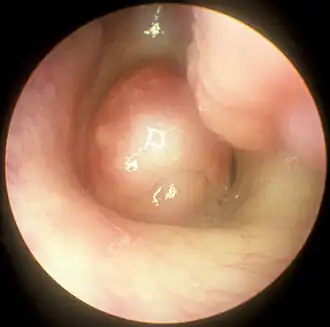

| Pólipo nasal em imagem captada por nasofibroscopia. | |

Pólipo nasal, também chamado polipose nasossinusal (PN) e pseudotumor nasossinusal, são formações polipóides não neoplásicas, pedunculadas e edematosas observadas nas cavidades nasais e seios paranasais em decorrência de um processo inflamatório crônico da mucosa nasal.[1][4][5][6] Geralmente de ocorrência bilateral, seus sintomas incluem obstrução nasal constante com dificuldade para respirar pelo nariz, perda do olfato, diminuição do paladar e secreção nasal anterior e posterior. Cefaleia e dor facial podem ocorrer, mas não são frequentes.[1][4] Entre as complicações geradas por essa patologia, uma das principais é a sinusite.[7][2]